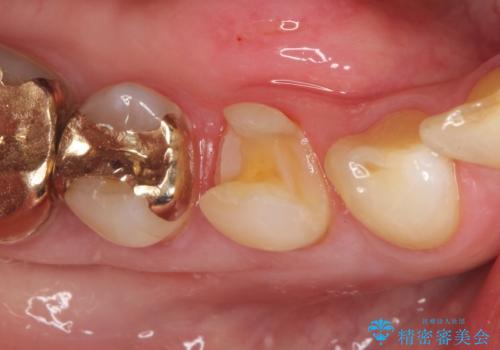

- 他院で治療した金属の詰め物が外れたことを主訴に来院されました。

PGAインレーにて修復治療を行いました。